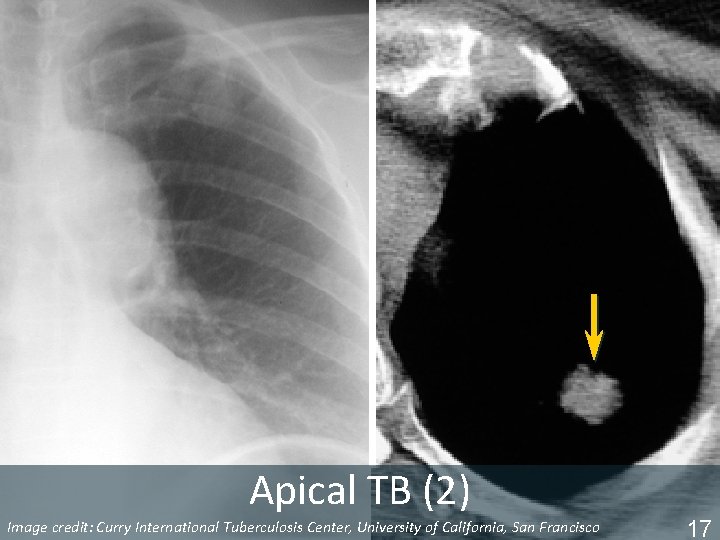

Worth a Second Look § § Apices Retrocardiac areas (left and right) Hilar regions Below diaphragm ISTC TB Training Modules 2009 15

Apical TB Image Tuberculosis Center, University of California, San Francisco ISTC TBcredit: Training Curry Modules. International 2009 16

Apical TB (2) Image Tuberculosis Center, University of California, San Francisco ISTC TBcredit: Training Curry Modules. International 2009 17